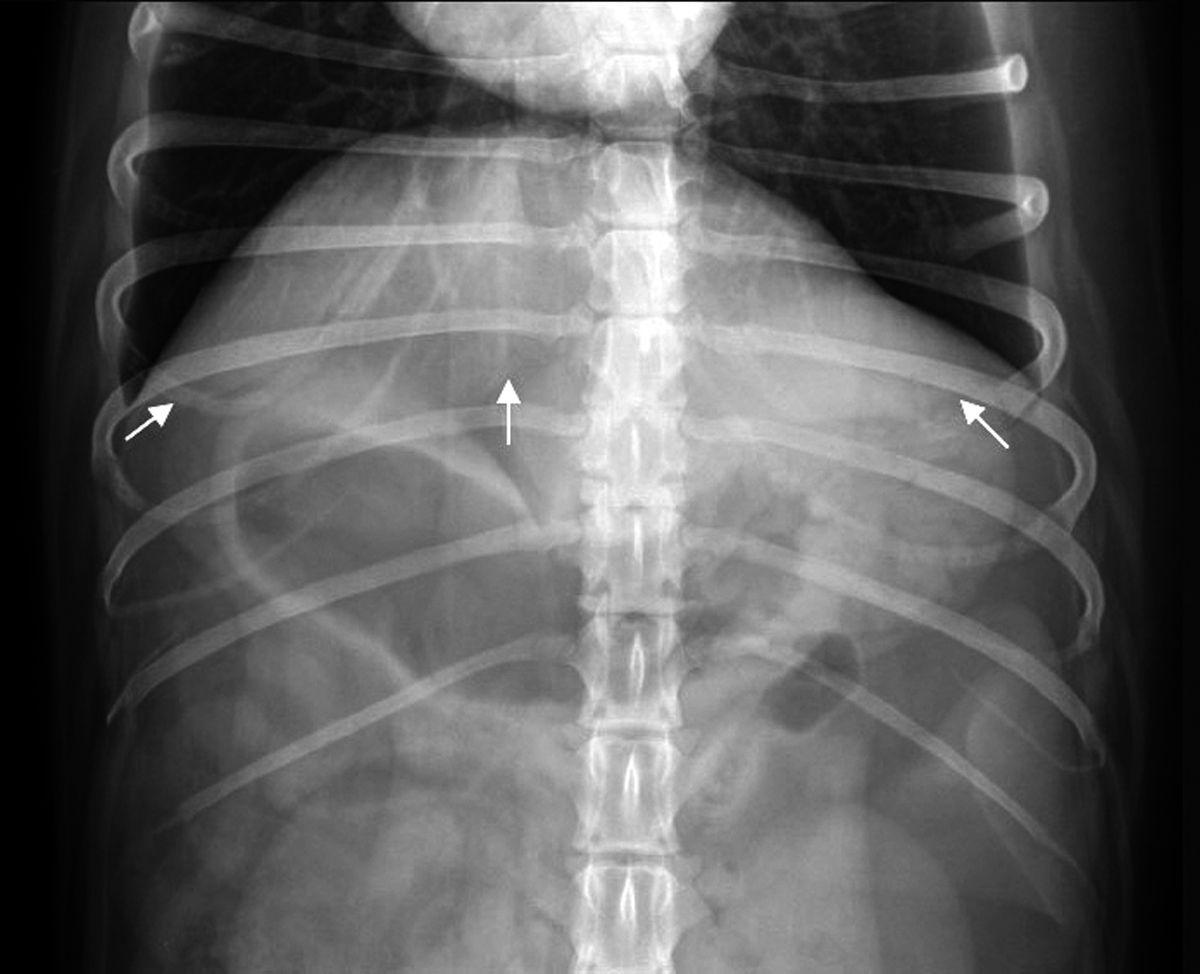

La silhouette epatica non può essere differenziata dal diaframma e viene delineata caudalmente dallo stomaco. L'aspetto caudoventrale del fegato normale ha margini netti (Figura 1a) (Figura 1b). L'asse gastrico può aiutare a valutare le dimensioni del fegato, dal momento che dovrebbe essere visibile in proiezione laterale nell'area compresa tra la linea tracciata a 90 gradi rispetto alla colonna vertebrale e quella parallela all'ultimo paio di coste. Si parla di epatomegalia quando l'asse gastrico è dislocato oltre l'ultimo paio di coste, o il margine caudoventrale del fegato si estende caudalmente alla faccia ventrale dello stomaco. Se lo stomaco è dislocato cranialmente, allora il fegato è probabilmente piccolo, anche se questo aspetto può essere normale nei cani a torace profondo (Boxer, Dobermann o Alano). Le epatopatie sono spesso associate ad ascite, che può precludere la valutazione del fegato, ma la presenza di fluido peritoneale, caratterizzato dalla perdita di definizione di sierosa e, nei casi gravi, dalla presenza di addome pendulo, è generalmente facile da riconoscere nelle radiografie addominali.

Radiografia addominale di un cane (proiezione ventrodorsale) che mostrano un fegato normale (frecce bianche). Il margine caudoventrale del fegato normale ha aspetto angolato.

Figura 1a. Radiografia addominale di un cane (proiezione ventrodorsale) che mostrano un fegato normale (frecce bianche). Il margine caudoventrale del fegato normale ha aspetto angolato.© Laurent Blond

Radiografia addominale di un cane (proiezione laterale) che mostrano un fegato normale (frecce bianche). Il margine caudoventrale del fegato normale ha aspetto angolato.

Figura 1b. Radiografia addominale di un cane (proiezione laterale) che mostrano un fegato normale (frecce bianche). Il margine caudoventrale del fegato normale ha aspetto angolato.© Laurent Blond